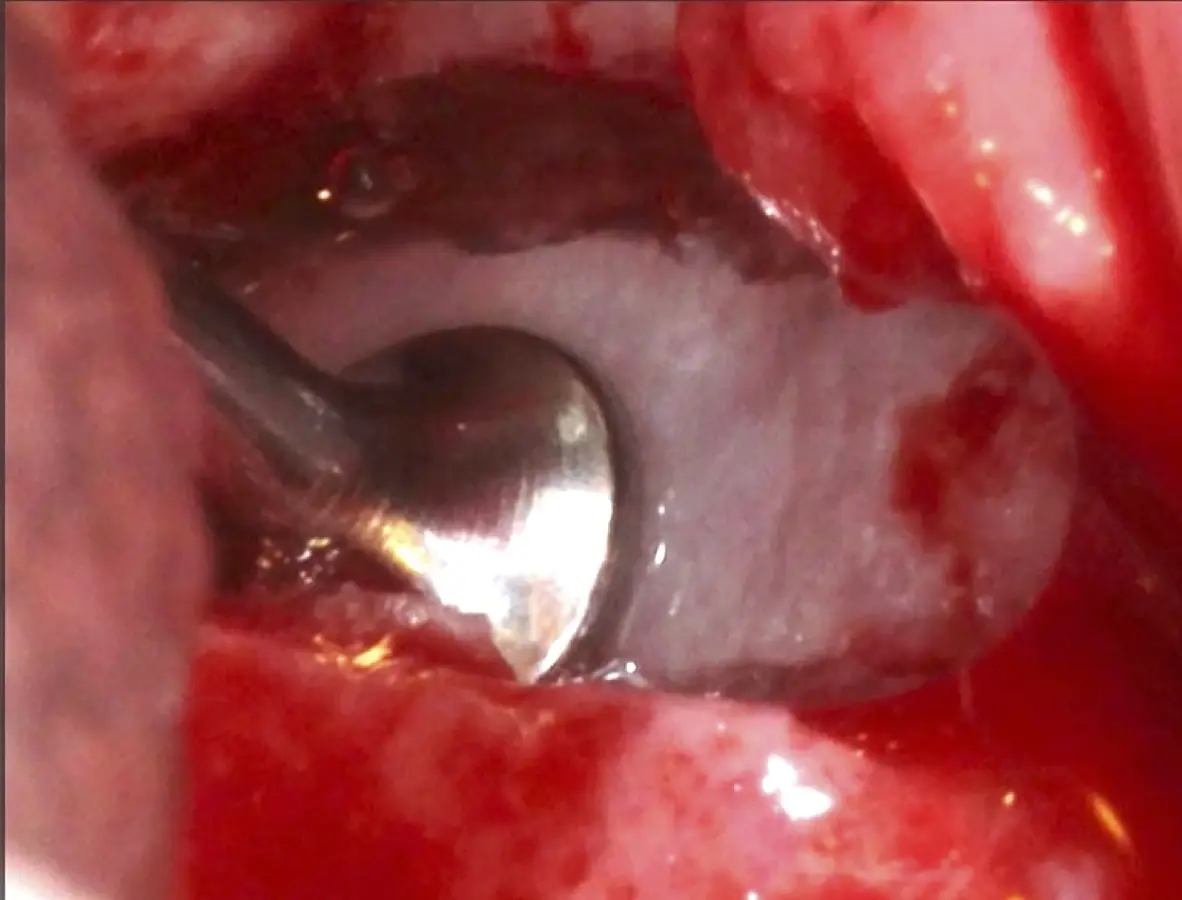

Se inicia la elevación de la membrana de Schneider con el inserto redondeado no cortante en forma de disco, empleando movimientos suaves. El levantamiento puede complementarse con elevadores convencionales, siguiendo la dirección mesiodistal. La fase de desprendimiento inicia con el piso y sigue hacia la pared mesial para terminar, y de ser necesario, hacia la pared posterior. Existen diversos insertos con angulaciones y longitudes para mayor accesibilidad16 (Figura 1).

Figura 1. Incisión y levantamiento de colgajo a espesor total.

Figura 3. Osteotomía por desgaste con inserto redondo de punta diamantada (a). Osteotomía por desgaste con inserto plano de punta diamantada (b). Osteotomía por corte con inserto plano de punta aserrada (c).